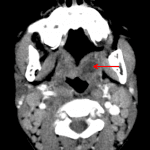

- Enlargement of the adenoid and palatine tonsils with striated enhancement

- Area of hypoattenuation in the lateral aspect of the left palatine tonsil without clear peripheral enhancement

- Mass effect on the nasopharynx and oropharynx, which remain patent

- Tonsillitis with phlegmon/early abscess

Enlarged adenoid and palatine tonsils with striated enhancement, consistent with acute tonsillitis. Area of hypoattenuation measuring 1 cm in the left palatine tonsil is concerning for phlegmon/developing abscess.

Mass effect on the nasopharynx and oropharynx, which remain patent.

Reactive cervical lymphadenopathy without suppuration. No retropharyngeal edema or venous thrombosis.